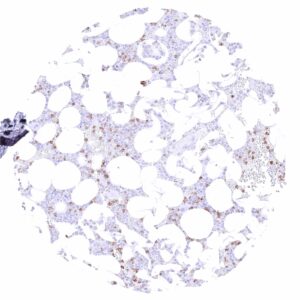

| Bone marrow/ lymphoid tissue | Bone marrow | Strong membranous CD35 staining of a subset of cells. |

In normal tissues, CD35 is most highly expressed in normal follicular dendritic cells, but it can also be seen on lymphocytes of various types, macrophages, granulocytes, and erythrocytes.